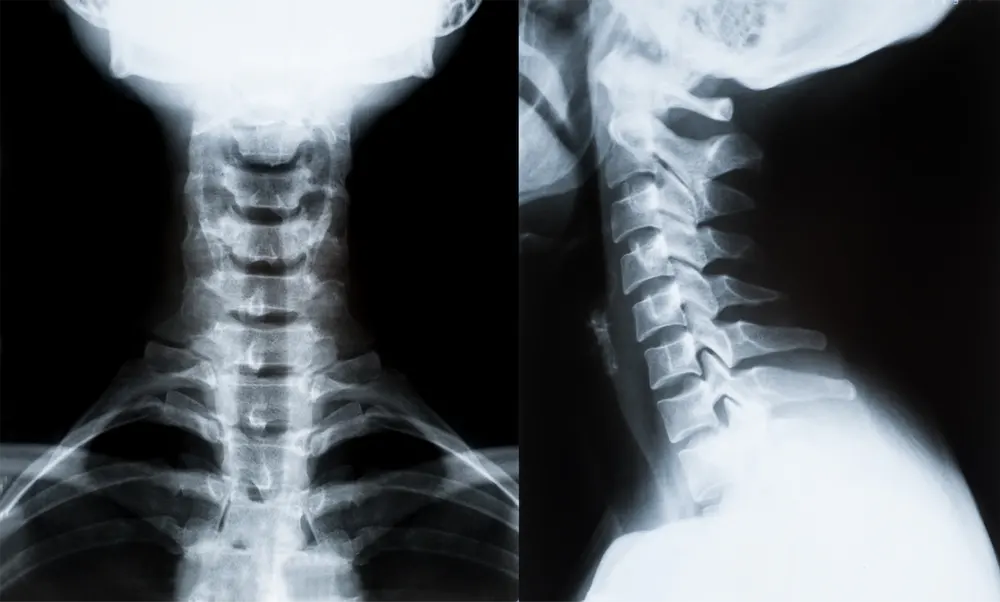

Rather than taking X-rays simply to confirm whether misalignment exists, we use imaging to quantify and measure the specific misalignment that has already been identified. This level of detail allows us to tailor corrections with exacting precision and avoid unnecessary intervention.

Postural and neurological observations

Precise imaging and measurements

Analysis of head and neck alignment